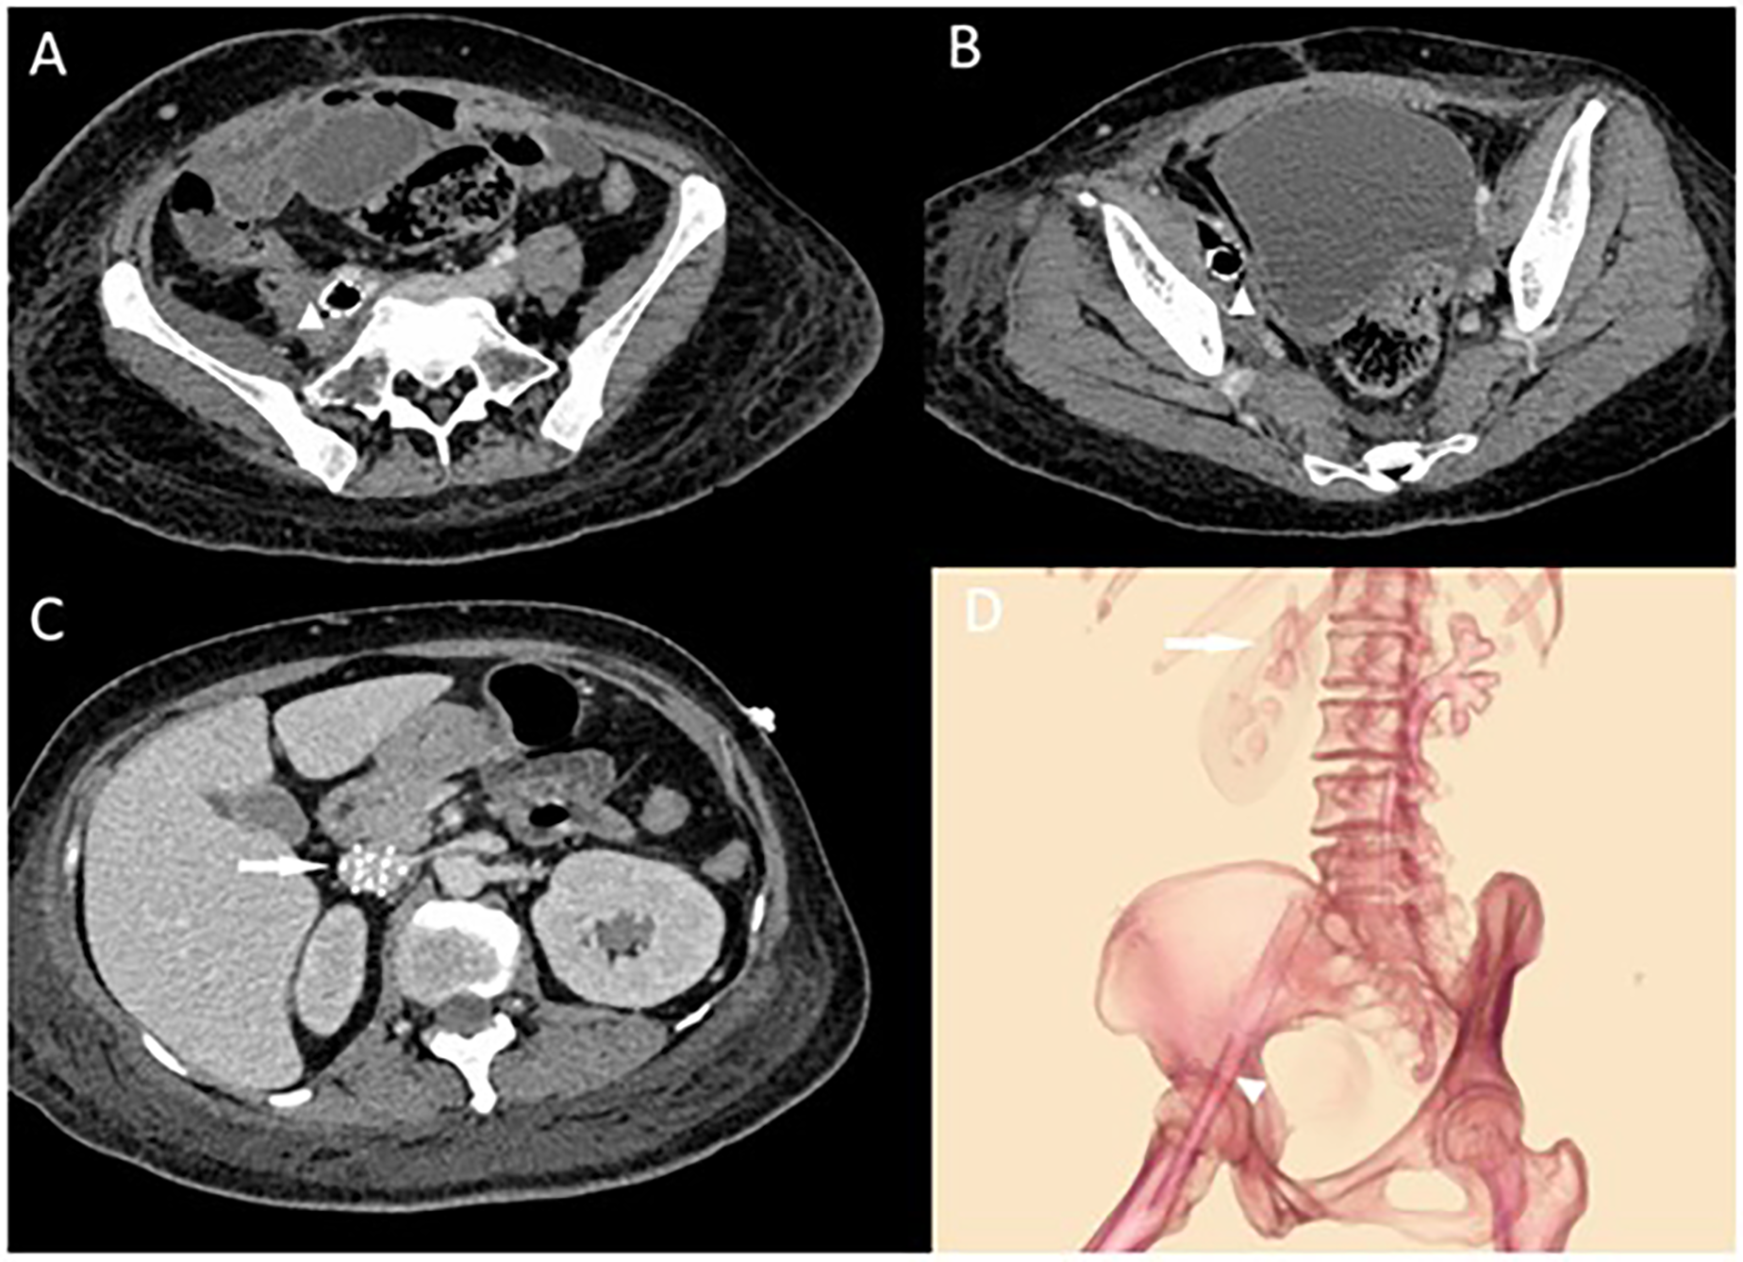

Laboratory tests revealed a normal white blood cell count (WBC) of 6.7 × 10⁹/L despite markedly elevated infection markers, including C-reactive protein (CRP) at 74.2 mg/L, interleukin-6 (IL-6) at 79.3 pg/ml, and procalcitonin (PCT) at 73.8 ng/ml, suggestive of a severe systemic inflammatory response. Meanwhile, pancytopenia was observed, with hemoglobin (Hb) at 51 g/L and platelet count (PLT) at 44 × 10⁹/L. Physical examination identified moderate pitting edema in the right lower limb and the foot below the left ankle. Blood cultures indicated dual infection with Escherichia coli and Enterococcus faecalis. Venous ultrasound suggested thrombosis in the right femoral and superficial femoral veins. An abdominal CT showed gas accumulation around the stent in the right external iliac and femoral veins with surrounding soft tissue swelling (Figure 1). We suspected an iliac vein stent infection leading to sepsis and planned an exploratory laparotomy to identify and manage the source of infection. Importantly, we decided against removing the filter during this hospital stay, planning its removal after assessing the risk of pulmonary embolism.

Figure 1

(A,B) Abdominal CT showing right external iliac vein and femoral vein stent with pneumatization and surrounding soft tissue swelling with pneumatization. The triangular markers indicate the abscess and the changes in the surrounding soft tissues around the stents. In (C), the arrow points to the locally placed inferior vena cava (IVC) filter situated within the IVC. (D) Illustrates the positions of the IVC filter and the two stents, showing their course crossing over the inguinal ligament.